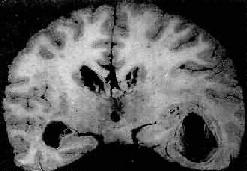

图16-10 化脓性脑膜炎 蛛网膜下腔内有多量脓液堆积以致大部分脑表面的沟回结构不清;脑膜血管高度扩张充血 镜下,蛛网膜血管高度扩张充血,蛛网膜下腔增宽,其中有大量中性粒细胞及纤维蛋白渗出和少量单核细胞、淋巴细胞浸润(图16-11)。用革兰染色,在细胞内外均可找到致病菌。脑膜及脑室附近脑组织小血管周围可见少量中性粒细胞浸润。病变严重者,动、静脉管壁可受累并进而发生脉管炎和血栓形成,从而导致脑实质的出血性梗死。

一、细菌性疾病(一)脑膜炎 脑膜炎(meningitis)可累有硬脑膜、蛛网膜和软脑膜。硬脑膜炎(pachymeningitis)多继发于颅骨感染。自从抗生素广泛应用以来,此病之发病率已大为减少。软脑膜炎包括蛛网膜和软脑膜炎症,则颇为常见。因此目前脑膜炎实际上是指软脑膜炎(leptomeningitis)而言。脑膜炎绝大部分由病原体引起,由脑膜炎双球菌引起的流行性脑膜炎是其中最主要的类型;少数则由刺激性化学药品(如普鲁卡因、氨甲蝶呤)引起。脑膜炎有3种基本类型:化脓性脑膜炎,淋巴细胞性脑膜炎(多由病毒引起),慢性脑膜炎(可由结核杆菌、梅毒螺旋体、布氏杆菌及真菌引起)。本节重点叙述化脓性脑膜炎。 1.急性化脓性脑膜炎急性化脓性脑膜炎是软脑膜的急性炎症,大量炎性渗出物积聚于蛛网膜下腔。其中流行性脑膜炎多在冬春季流行,其余病原的脑膜炎则多为散发性。 【病因和发病机制】 急性化脓性脑膜炎的致病菌类型随患者之年龄而异。在青少年患者中以脑膜炎双球菌感染为主。该菌存在于病人和带菌者的鼻咽部,借飞沫经呼吸道传染,细菌进入上呼吸道后,大多数只引起局部炎症,成为健康带菌者;仅小部分机体抵抗力低下的患者,细菌可从上呼吸道粘膜侵入血流,并在血液中繁殖,到达脑脊膜后引起脑膜炎。在冬春季可形成流行,称为流行性脑膜炎。 新生儿脑膜炎最常见的病因是大肠杆菌,感染多来自产道。由于体内缺乏能中和病菌的IgM,入侵的大肠杆菌得以繁殖而致病。 流感杆菌脑膜炎多见于3岁以下之婴幼儿。肺炎球菌脑膜炎在幼儿和老年人常见,其中幼儿的脑膜感染多来自中耳炎,而在老人则常为大叶性肺炎的一种并发症。 【病理变化】 肉眼观,脑脊膜血管高度扩张充血,病变严重的区域,蛛网膜下腔充满灰黄色脓性渗出物,覆盖着脑沟脑回,以致结构模糊不清(图16-10),边缘病变较轻的区域,可见脓性渗出物沿血管分布。在渗出物较少的区域,软脑膜往往略带混浊。脓性渗出物可累及大脑凸面矢状窦附近或脑底部视神经交叉及邻近各池。由于炎性渗出物的阻塞,使脑脊液循环发生障碍,可引起不同程度的脑室扩张。